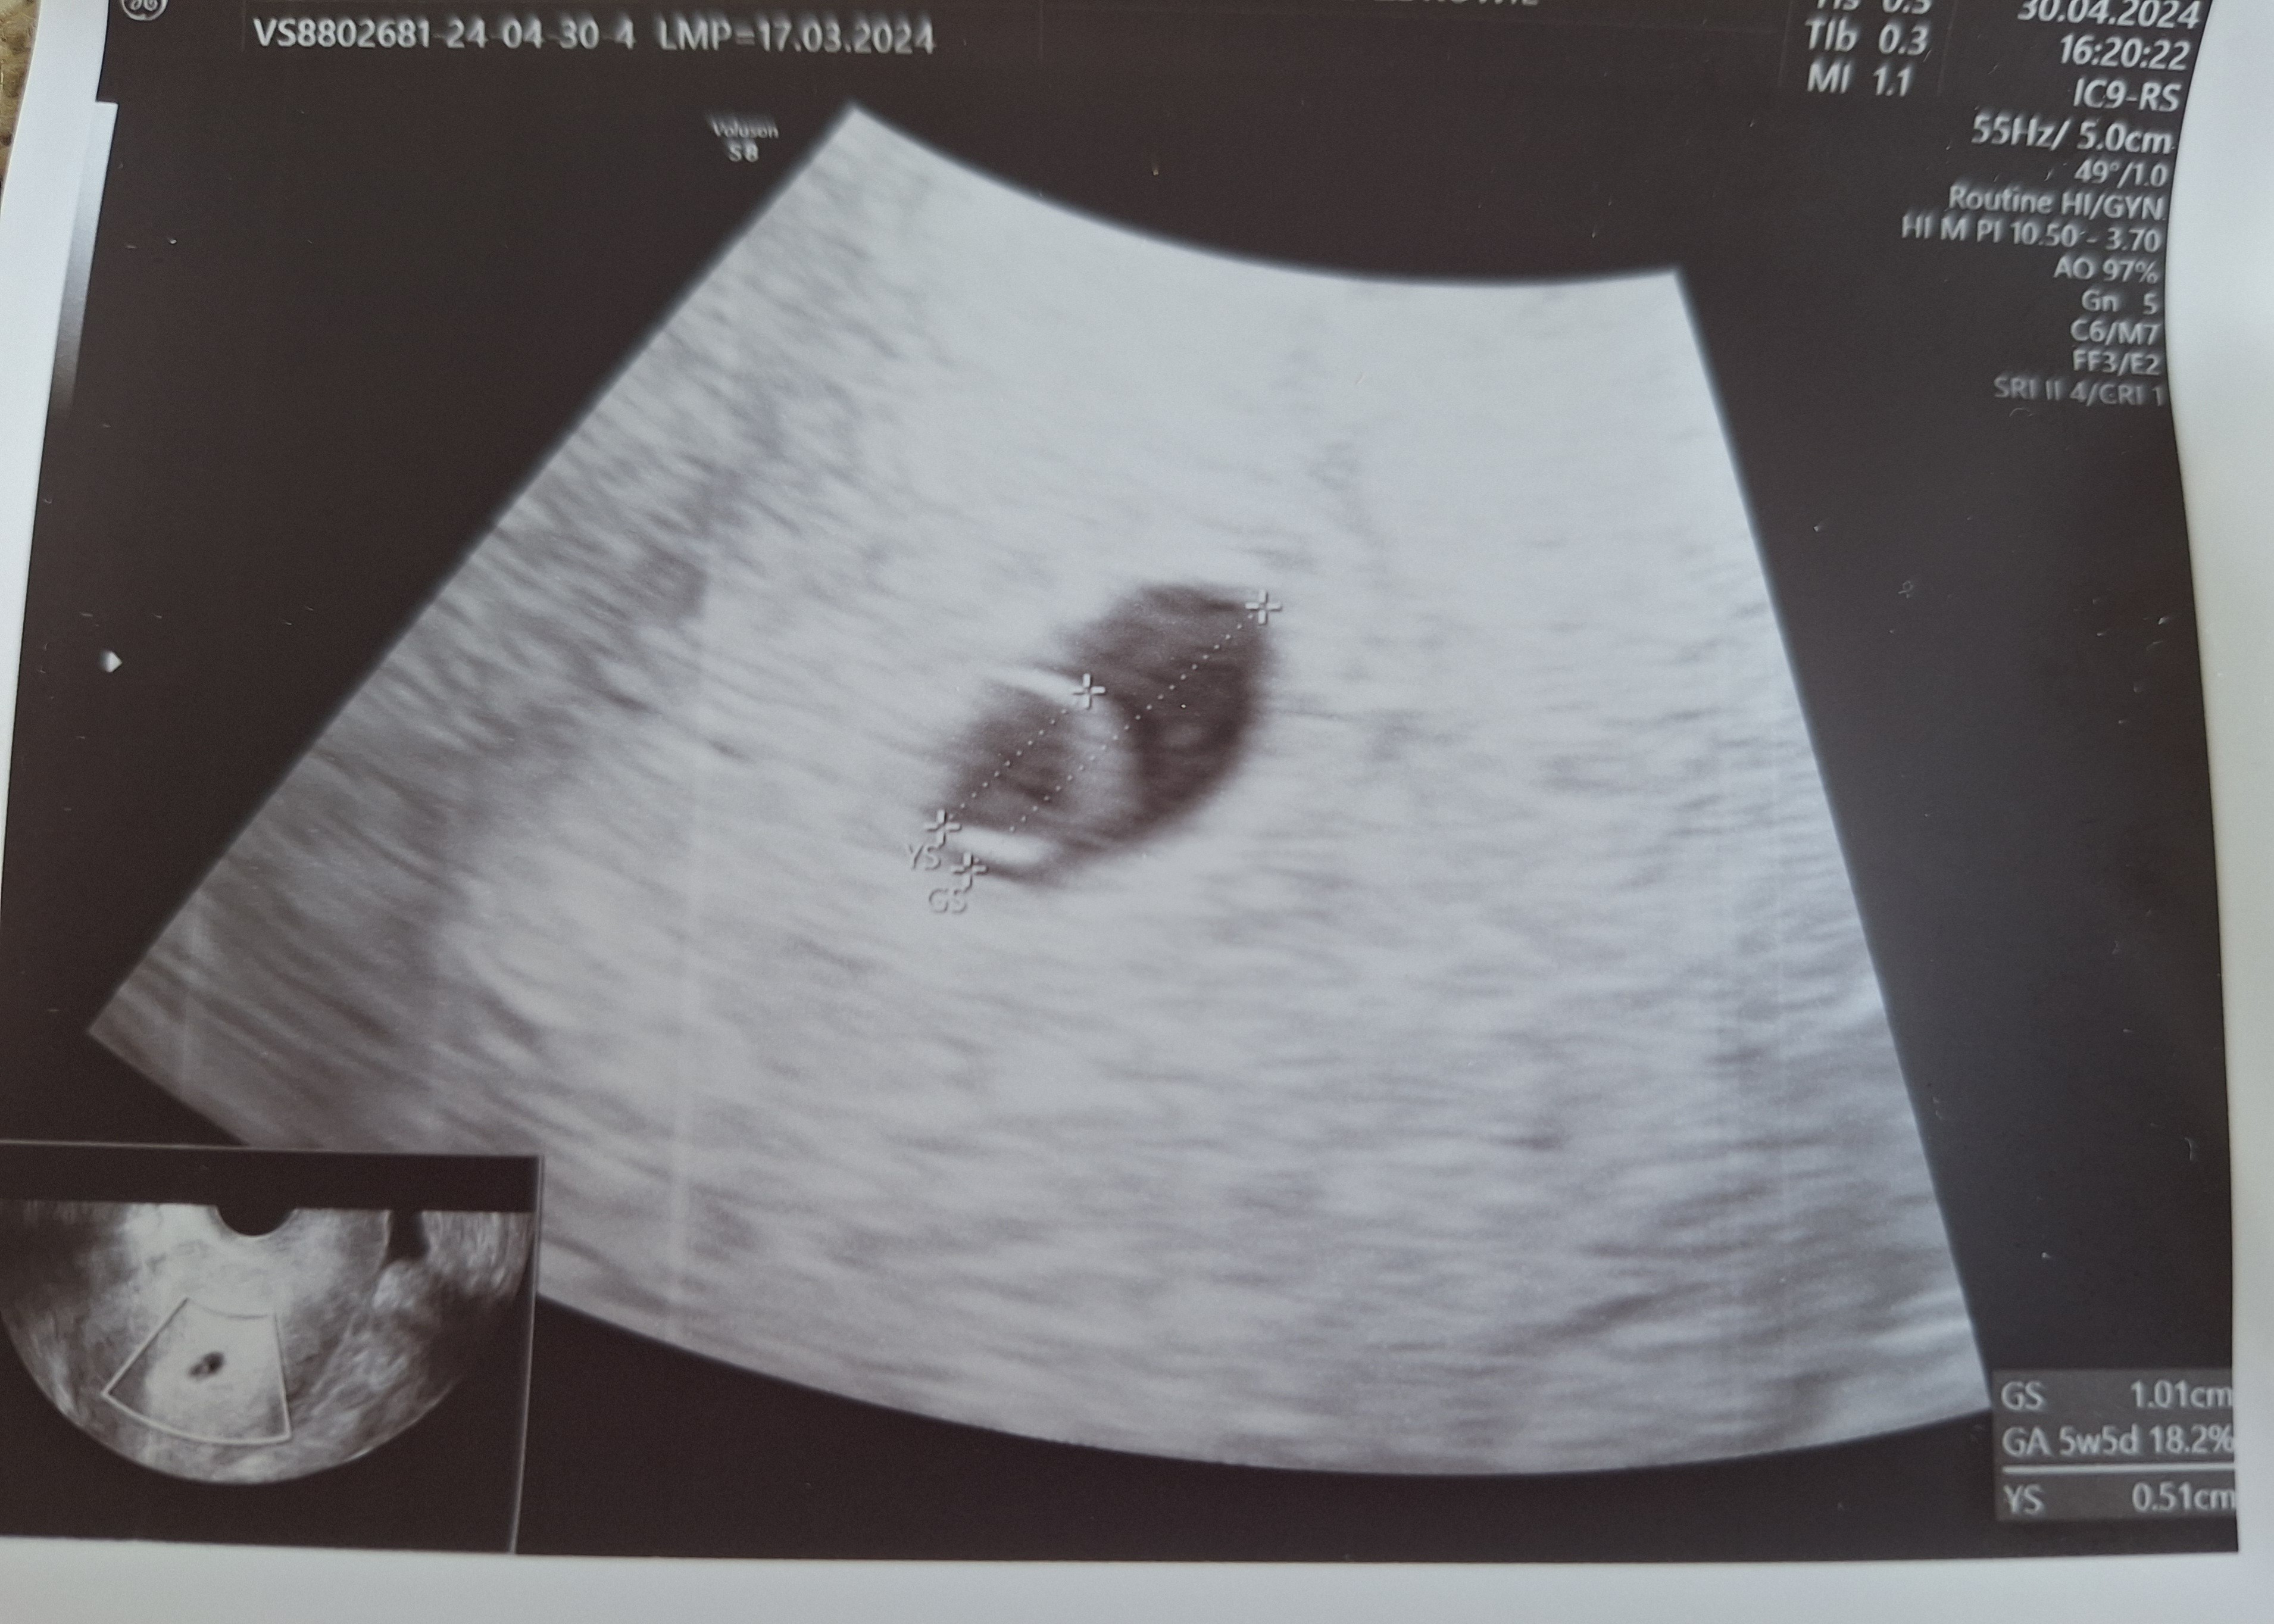

Po ostatniej wizycie na PZU w zeszły czwartek (wg mnie 5+3) był widoczny pecherzyk 5+2 (więc niby okej, jeden dzień różnicy), ale bez widocznego pęcherzyka żółtkowego i zarodka. Lekarz kazał przyjść za tydzień, ale ponieważ gabinety zamknięte, bo majówka, to byłam wczoraj, we wtorek, wg mnie to było 6+1. Na USG widoczny pęcherzyk ciążowy 1,01 cm 5+5 ( czyli 3 dni różnicy z wymiaru) z pęcherzykiem żółtkowym 0,51 mm... zarodka nie widać. Niby w jednym miejscu lekarz pokazywał, że tam może być zarodek, no ale nie było co mierzyć, bo za małe. Czy dobrze myślę, że ten pęcherzyk żółtkowy jest za duży jak na taki wiek ciąży i na taki rozmiar pęcherzyka ciążowego? Jeszcze myślę, że może kiepskie ujęcie, bo ścianki YS są mocno pogrubione a zmierzone jakby po zewnętrznej, ale mimo wszystko, w czwartek nie było w środku nic a po 5 dniach nagle taki duży YS? Lekarz był bardzo młody, jeszcze chyba w trakcie specjalizacji, bardzo się starał i był uważny, ale chyba trochę popłynął mówiąc, że pecherzyk żółtkowy o wymiarach połowy pęcherzyka ciążowego to dobry znak... Co sądzicie?

Beta z wczoraj 9530 (wtorek, 30.04), ostatnia z ubiegłego poniedziałku (22.04) 1540.

Dołączam zdjęcia usg z czwartku i wtorku.